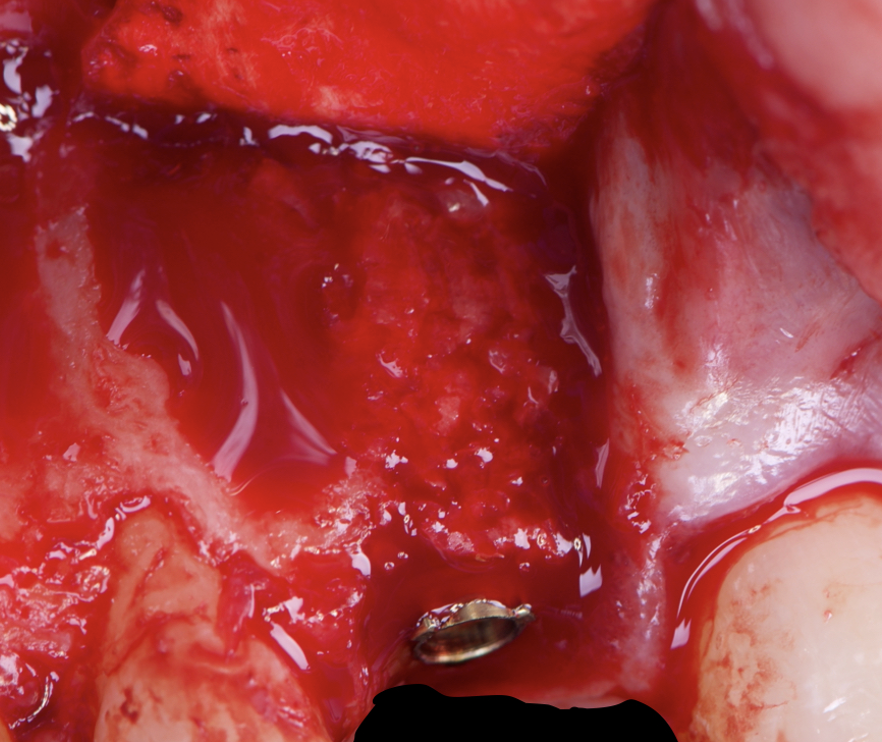

Given the significant buccal defect, guided bone regeneration (GBR) was performed simultaneously. A mixture of autologous bone and creos™ xenogain™ was applied to the defect and covered with a resorbable creos™ membrane to restore ridge width and support the buccal contour. In addition, a connective tissue graft was harvested and placed in the vestibular region to increase the thickness of keratinized mucosa. This combined approach addressed both hard and soft tissue deficiencies, providing the biological foundation for a stable and esthetic outcome.